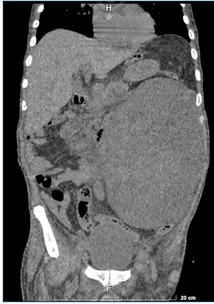

Por consiguiente, se procede a realizar tomografía abdominopélvica axial computarizada con contraste endovenoso, la cual reporta tumoración ovalada retroperitoneal de 19.55 x 10.90, con volumen aproximado de 3300cc con densidades mixtas, que ocupa hemiabdomen izquierdo, sugerida como hematoma retroperitoneal en el reporte oficial del estudio (Fig.1) y (Fig. 2).

Fig.2.  Tomografía axial computarizada con contraste abdominopélvica en corte coronal. Muestra masa de densidades mixtas

Los leiomiosarcomas se evidencian como extensas áreas de heterogeneidad y realce heterogéneo, ocasionado por la presencia de necrosis y focos hemorrágicos.

Generalmente no hay presencia de calcificaciones y hay ausencia de tejido adiposo, de esta manera, se puede inferir que una gran masa retroperitoneal mayor a 10 cm sin contenido graso y necrosis interna variable debe sugerir la posibilidad de un leiomiosarcoma. 3,4,10Respecto al caso presentado la evaluación inicial se realizó mediante la realización de un USG Doppler, el cual fue sugestivo de una imagen compatible con hematoma retroperitoneal, lo que llevo a la toma de una tomografía abdominopélvica contrastada, con densidades mixtas, lo cual apoyaba más la impresión diagnóstica de un hematoma retroperitoneal según lo indicado en el reporte oficial.